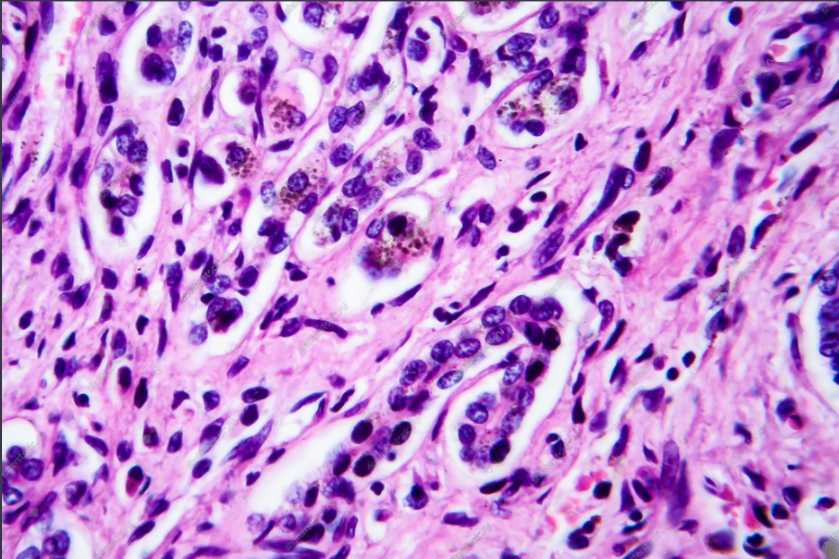

Tissue Cross-Reactivity. (Creative Biolabs Authorized)

Tissue cross-reactivity (TCR) studies are an important aspect of pre-clinical development of therapeutic antibodies. Non-target specific binding to human tissue can result in serious consequences when pharmacologically active antibodies (Ab) are used to treat diseases. Therefore, prior to Phase I clinical trials, cross-reactivity studies of therapeutic Ab candidates are performed to identify cross-reactive or non-target tissue binding, which in turn provides important information about the immunological properties of the candidate antibody therapeutics.

Creative Biolabs' TCR services support the development of your candidate therapeutic antibodies by providing a powerful immunohistochemical assessment of potential cross-reactivity with a range of human tissue.